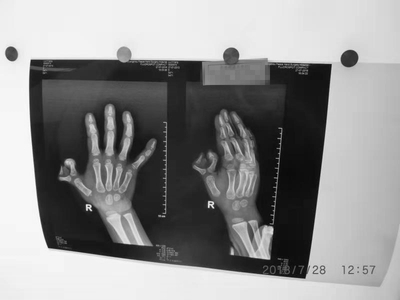

性别:男     年龄:8个月      双手并指畸形

诊断:双手并指畸形,伴活动障碍,需进行并指分指手术